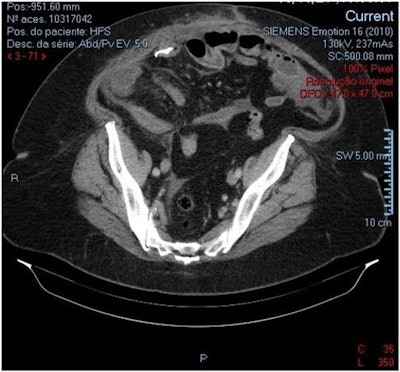

An abdominal and pelvic CT scan showed an endoluminal metallic object in the right lower quadrant, and clinicians asked the patient whether she had swallowed a fish bone or ingested any foreign objects, including dentures. She did not remember ingesting anything unusual, the authors wrote.